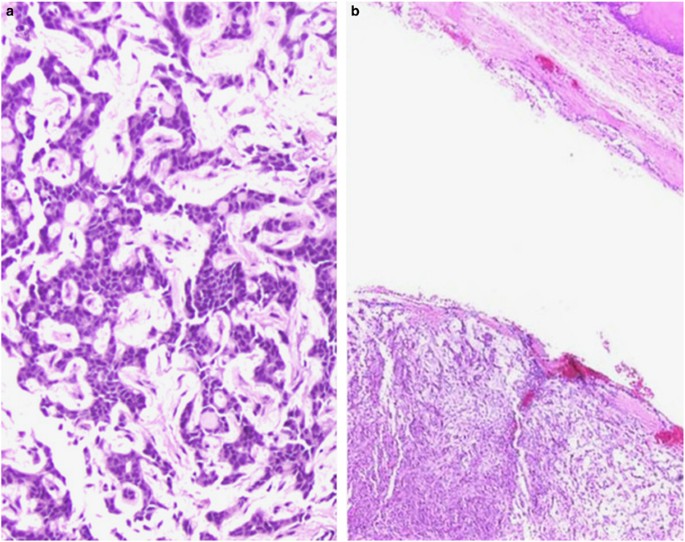

However, primary pleomorphic basaloid salivary tumors exist, and usually represent high-grade transformation (HGT) of another low-grade tumor type, which not surprisingly, is often basaloid to begin with.32 ACC, EMCA, acinic cell carcinoma, and PLGA/CASG represent basaloid tumor types that are documented to undergo HGT.32, 33, 34, 35, 36, 37 As this designation implies, these variants behave more aggressively than their purely conventional counterparts. Surprisingly, the transformed components for all these tumor types looks remarkably similar, with ductal components predominating and demonstrating the appearance of a high-grade adenocarcinoma, or undifferentiated carcinoma. In general, the biphasic nature in HGT is lost, but it can be retained in EMCA.36 HGT in any tumor type is often accompanied by necrosis and desmoplasia (Figure 8). As the morphology can be non-descript, the most reliable method to establish diagnosis is recognition of the conventional component.

The differential diagnoses for basaloid salivary gland tumors with HGT includes salivary duct carcinoma, metastatic basaloid, and non-keratinizing squamous cell carcinoma (SCC), and non-salivary non-epithelial lesions. Salivary duct carcinoma may resemble any given basaloid tumor with HGT, as it is a pleomorphic adenocarcinoma that often shows necrosis and desmoplasia. The fundamental difference is that salivary duct carcinoma is an apocrine tumor and is thus ‘pink’ rather than blue. In addition, given this apocrine phenotype, it is characteristically androgen receptor (AR) positive. Most AR-negative tumors labeled as salivary duct carcinoma actually represent HGT of other entities, such as those noted above.38 Basaloid as well as non-keratinizing SCC can resemble salivary gland tumors ranging from ACC to BCAC. At minor salivary sites, primary basaloid or non-keratinizing SCC enters the differential diagnosis, while in parotid, metastasis enters the differential diagnosis. At primary sites, a surface or in situ component is a critical distinguishing factor since a primary salivary gland tumor is not expected to show this. When a metastasis is being considered, clinical history and immunohistochemical workup may be required. Notably non-keratinizing SCC metastases may masquerade as basaloid tumors (Figure 9). Rarely neuroendocrine carcinomas (metastases and rare primaries), as well as sarcomas (desmoplastic small round cell tumor, adamantinoma-like Ewing sarcoma, and biphasic synovial sarcoma) may enter the differential diagnosis.39 These are not usually intuitive initial diagnostic considerations, but warrant consideration if the typically salivary type entities are excluded, and the immunophenotype is not as expected.